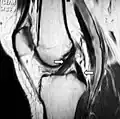

Magnetic resonance imaging evaluation demonstrating normal signal of both anterior and posterior cruciate ligaments (arrows).